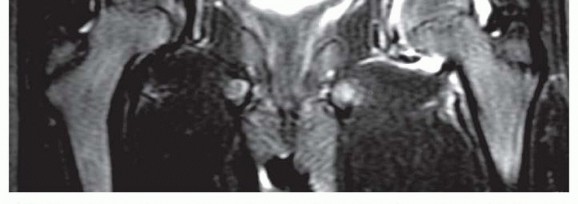

In the early stage, synovitis is observed, collapse and deformity of the cartilage of the epiphysis is usually clearly visible, and the degree of hinged subluxation (impingement) can be determined (

FIG 3

).18

FIG 3 • Magnetic resonance image of the hip of a patient with Perthes disease showing lateral subluxation, synovitis, and acetabular-femoral impingement (hinged subluxation).